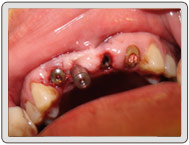

治療中

植入植體